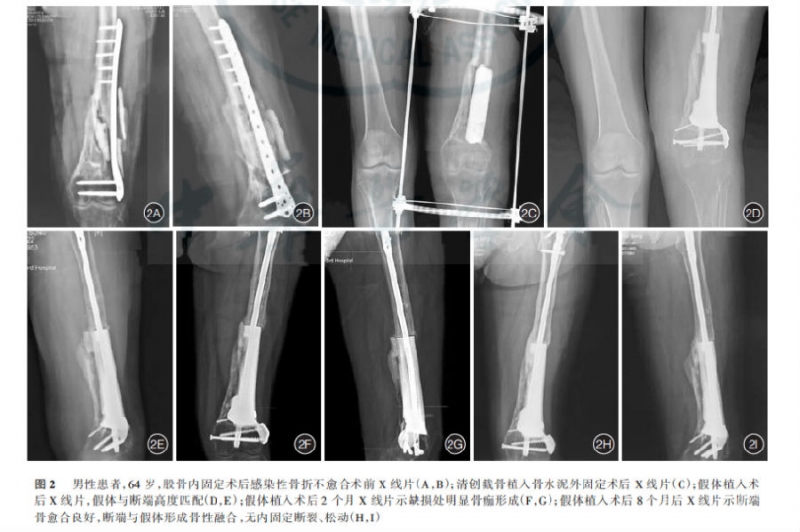

材料与方法:采用3D打印技术治疗因创伤或手术内固定失败造成的下肢慢性骨髓炎患者8例,病因:交通伤5例,内固定术后3例;缺损部位:股骨干5例,股骨干骺端1例,胫骨干1例,胫骨干骺端1例;缺损长度:7.7-15.5cm,平均10.2cm;分泌物培养:金黄色葡萄菌3例,表皮葡萄球菌2例,摩尔摩根1例,无感染2例。所有患者按3D打印技术治疗的标准流程分3阶段完成手术治疗。

结果:8例患者术后随访6-18个月(平均12.6个月)。8例患者感染灶控制,无体温升高,窦道愈合,感染指标均在正常范围内,血常规、ESR、C-反应蛋白及PCT,3次以上化验结果正常,连续3次留取引流液细菌培养阴性,随访无复发。

患者从第一次入院到假体置入完成后出院,总治疗时间为65-125d(平均91.0d)。第一阶段局部感染控制及临时稳定重建接受治疗时间13-57d(平均28.7d),第二阶段假体及稳定模式设计用时30-87d(平均48.3d),第三阶段假体与骨之间生物学稳定及融合所需时间28-34d(平均63.0d),无内固定物松动及断裂。7例患者在假体置入术后14.7d(4-42d)恢复完全负重活动,1例患者因有严重骨质疏松症术后6个月恢复完全负重。8例患者术后关节功能恢复良好。

图2: 典型病例